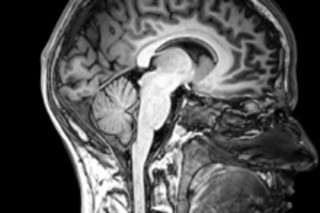

Not just yet. The day probably will come when functional MRI brain scans become viable evidence in American courts, but thanks to a ruling in a Brooklyn case this week, that day is yet to come. DISCOVER covered the details of the case two weeks ago—a woman sued her former employer claiming she was treated poorly after complaining of sexual harassment, and wanted fMRI scans admitted as evidence to validate the credibility of a witness. But Judge Robert H. Miller has now denied the request under New York State's Frye test, which says, among other things, that expert testimony is only admissible if it's widely accepted in the scientific community. As we saw yesterday when we covered the optogenetics tests designed to verify fMRI results, there are still lingering doubts about the technique's reliability. Given that there were apparently no other rulings that dealt with the admissibility of fMRI (at least as far as the lawyers could find), Judge Miller declined to be the first to allow it.

But a similar fMRI battle is under way in Tennessee. Cephos, the same company that provided the brain scans in the Brooklyn case, is involved here, and CEO Steven Laken testified about the validity of his technology on Friday.

Late last year, Cephos was retained by the defendant in the Tennessee case, Lorne Semrau, a psychologist who is fighting charges that he defrauded Medicare and other health insurers with wrongful claims. Semrau's attorney hopes to introduce fMRI scans performed by Cephos as evidence that he is telling the truth when he says he had no intent to commit fraud [ScienceInsider].